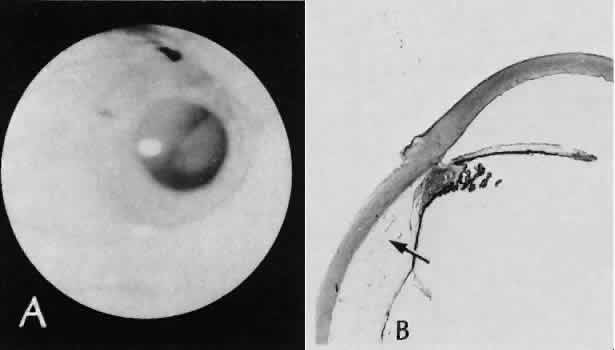

Epithelial downgrowth (ingrowth) (Fig. 44) is one of the most serious causes of pseudophakic glaucoma, in which surface epithelium (probably from the conjunctiva) grows into the anterior chamber. This condition is more likely to occur with fornix-based conjunctival flaps than with limbus-based flaps and in eyes with problems in wound closure, such as vitreous loss, wound incarceration of tissue, delayed reformation of the anterior chamber, or frank rupture of the limbal incision, and when instruments such as iridectomy forceps are contaminated with surface epithelium before they are introduced into the eye. Epithelial downgrowth causes an anterior chamber angle closure by means of peripheral anterior synechiae or lines an open anterior chamber angle and obstructs aqueous outflow mechanically. Histologically, the epithelium is seen to grow most luxuriously and in multiple layers on the iris where there is a good blood supply, but it tends to grow sparsely and in a single layer on the posterior surface of the avascular cornea. The epithelium may extend behind the iris, over the ciliary body, and even far into the interior of the eye.

Fig. 44. A case of epithelial downgrowth. A. The clinical findings are subtle and consist of a translucentmembrane on the posterior corneal surface, often contiguous with an ocular wound, characterized by a well-defined, linear leading edge. In this case, the leading edge is just above the corneal light reflex. B. In contrast, in this case, the leading edge is just below the corneal light reflex. The surgical procedure in both cases appears to have been complicated because of the presence of sector iridectomies. C. In this case, surface stratified squamous epithelium lines the posterior cornea (including the posterior aspect of the clear corneal wound) and extends over delicate trabecular tissue onto the anterior surface of the iris. The epithelium will adapt the tissue over which it grows to produce an adhesive surface appropriate to its attachment requirements. This adaptive process that is an advantage for the epithelium will permanently destroy the function of the trabecular meshwork over which the surface epithelium extends. D. The actual site of the fistula allowing the epithelium to gain access to the internal surfaces of the eye is rarely found on histologic sections. Higher magnification of the area of the wound, however, does show the presence of foreign material in the incision. Polarized material (inset) consistent with degenerating silk suture is present. Invasion of the epithelium along a suture tract is one possible route of entrance. (Hematoxylin-eosin stain with and without polarization; A, × 21; B, × 101)